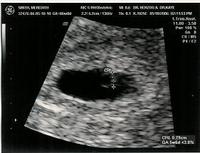

So here’s a first look. Due on January 11th.

The line drawn is the baby. Not much to see…only 3 mm in size. But the heart was pumping strong…that was amazing.